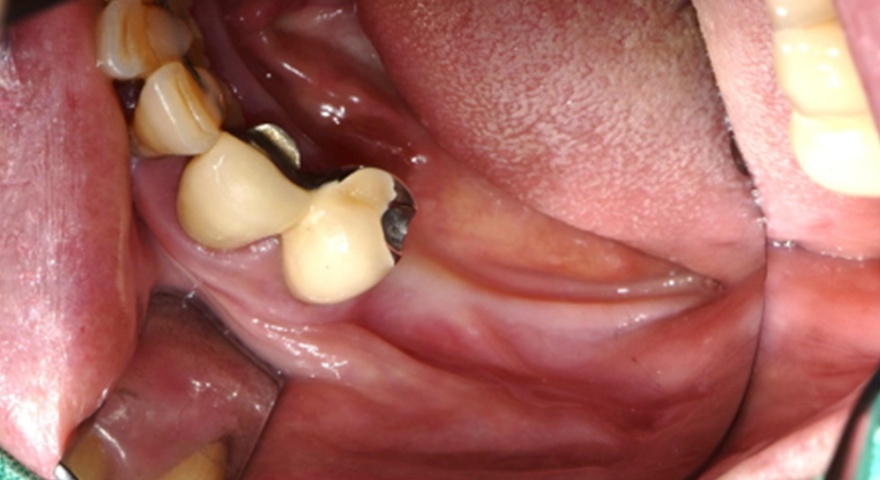

Проблема дегісценції кісткової тканини навколо імплантатів з боку щоки є актуальною, особливо в умовах обмеженого об’єму залишкової кістки. Це дослідження спрямоване на перевірку ефективності двошарового підходу до аугментації, що поєднує пастоподібний та гранульований ксеногенний матеріал, покритий колагеновою мембраною. Такий підхід застосували для відновлення ділянок оголеної різьби імплантатів. У дослідженні взяли участь троє пацієнтів, для аналізу було відібрано три імплантати. Середній показник BIC сягнув понад 67 %.

У рамках проспективного дослідження троє пацієнтів із частковою або повною адентією отримали загалом 17 імплантатів, з яких три — в ділянки з вираженими дефектами букальної кістки. Ці імплантати були вилучені через шість місяців для аналізу. При аугментації застосовували формопластичний остеоматеріал (S1) та гранульований матеріал (BOSS), які покривали колагеновою мембраною (COLLA). Всі матеріали були бичачого походження. Стан кісткової інтеграції аналізували гістологічно та гістоморфометрично.

Клінічно спостерігалося повне загоєння без ускладнень. Не було зафіксовано випадків десісценції, інфекцій чи оголення мембран. Всім пацієнтам були встановлені постійні ортопедичні конструкції на імплантатах.

Рис. 2. (A) Пацієнт із виявленою необмеженою (non-contained) втратою кісткової тканини та оголенням імплантату з букального боку на момент встановлення імплантату. (B) Нанесення основного шару пастоподібного кісткового матеріалу перед внесенням гранульованого кісткового трансплантата. (C) Укладання колагенової мембрани з покриттям зони трансплантації — від букального до піднебінного боку — та фіксували за допомогою внутрішніх періостальних швів. (D) Через шість місяців після аугментації — візуалізується регенерація кістки з букального боку в ділянці раніше оголеної різьби імплантату.